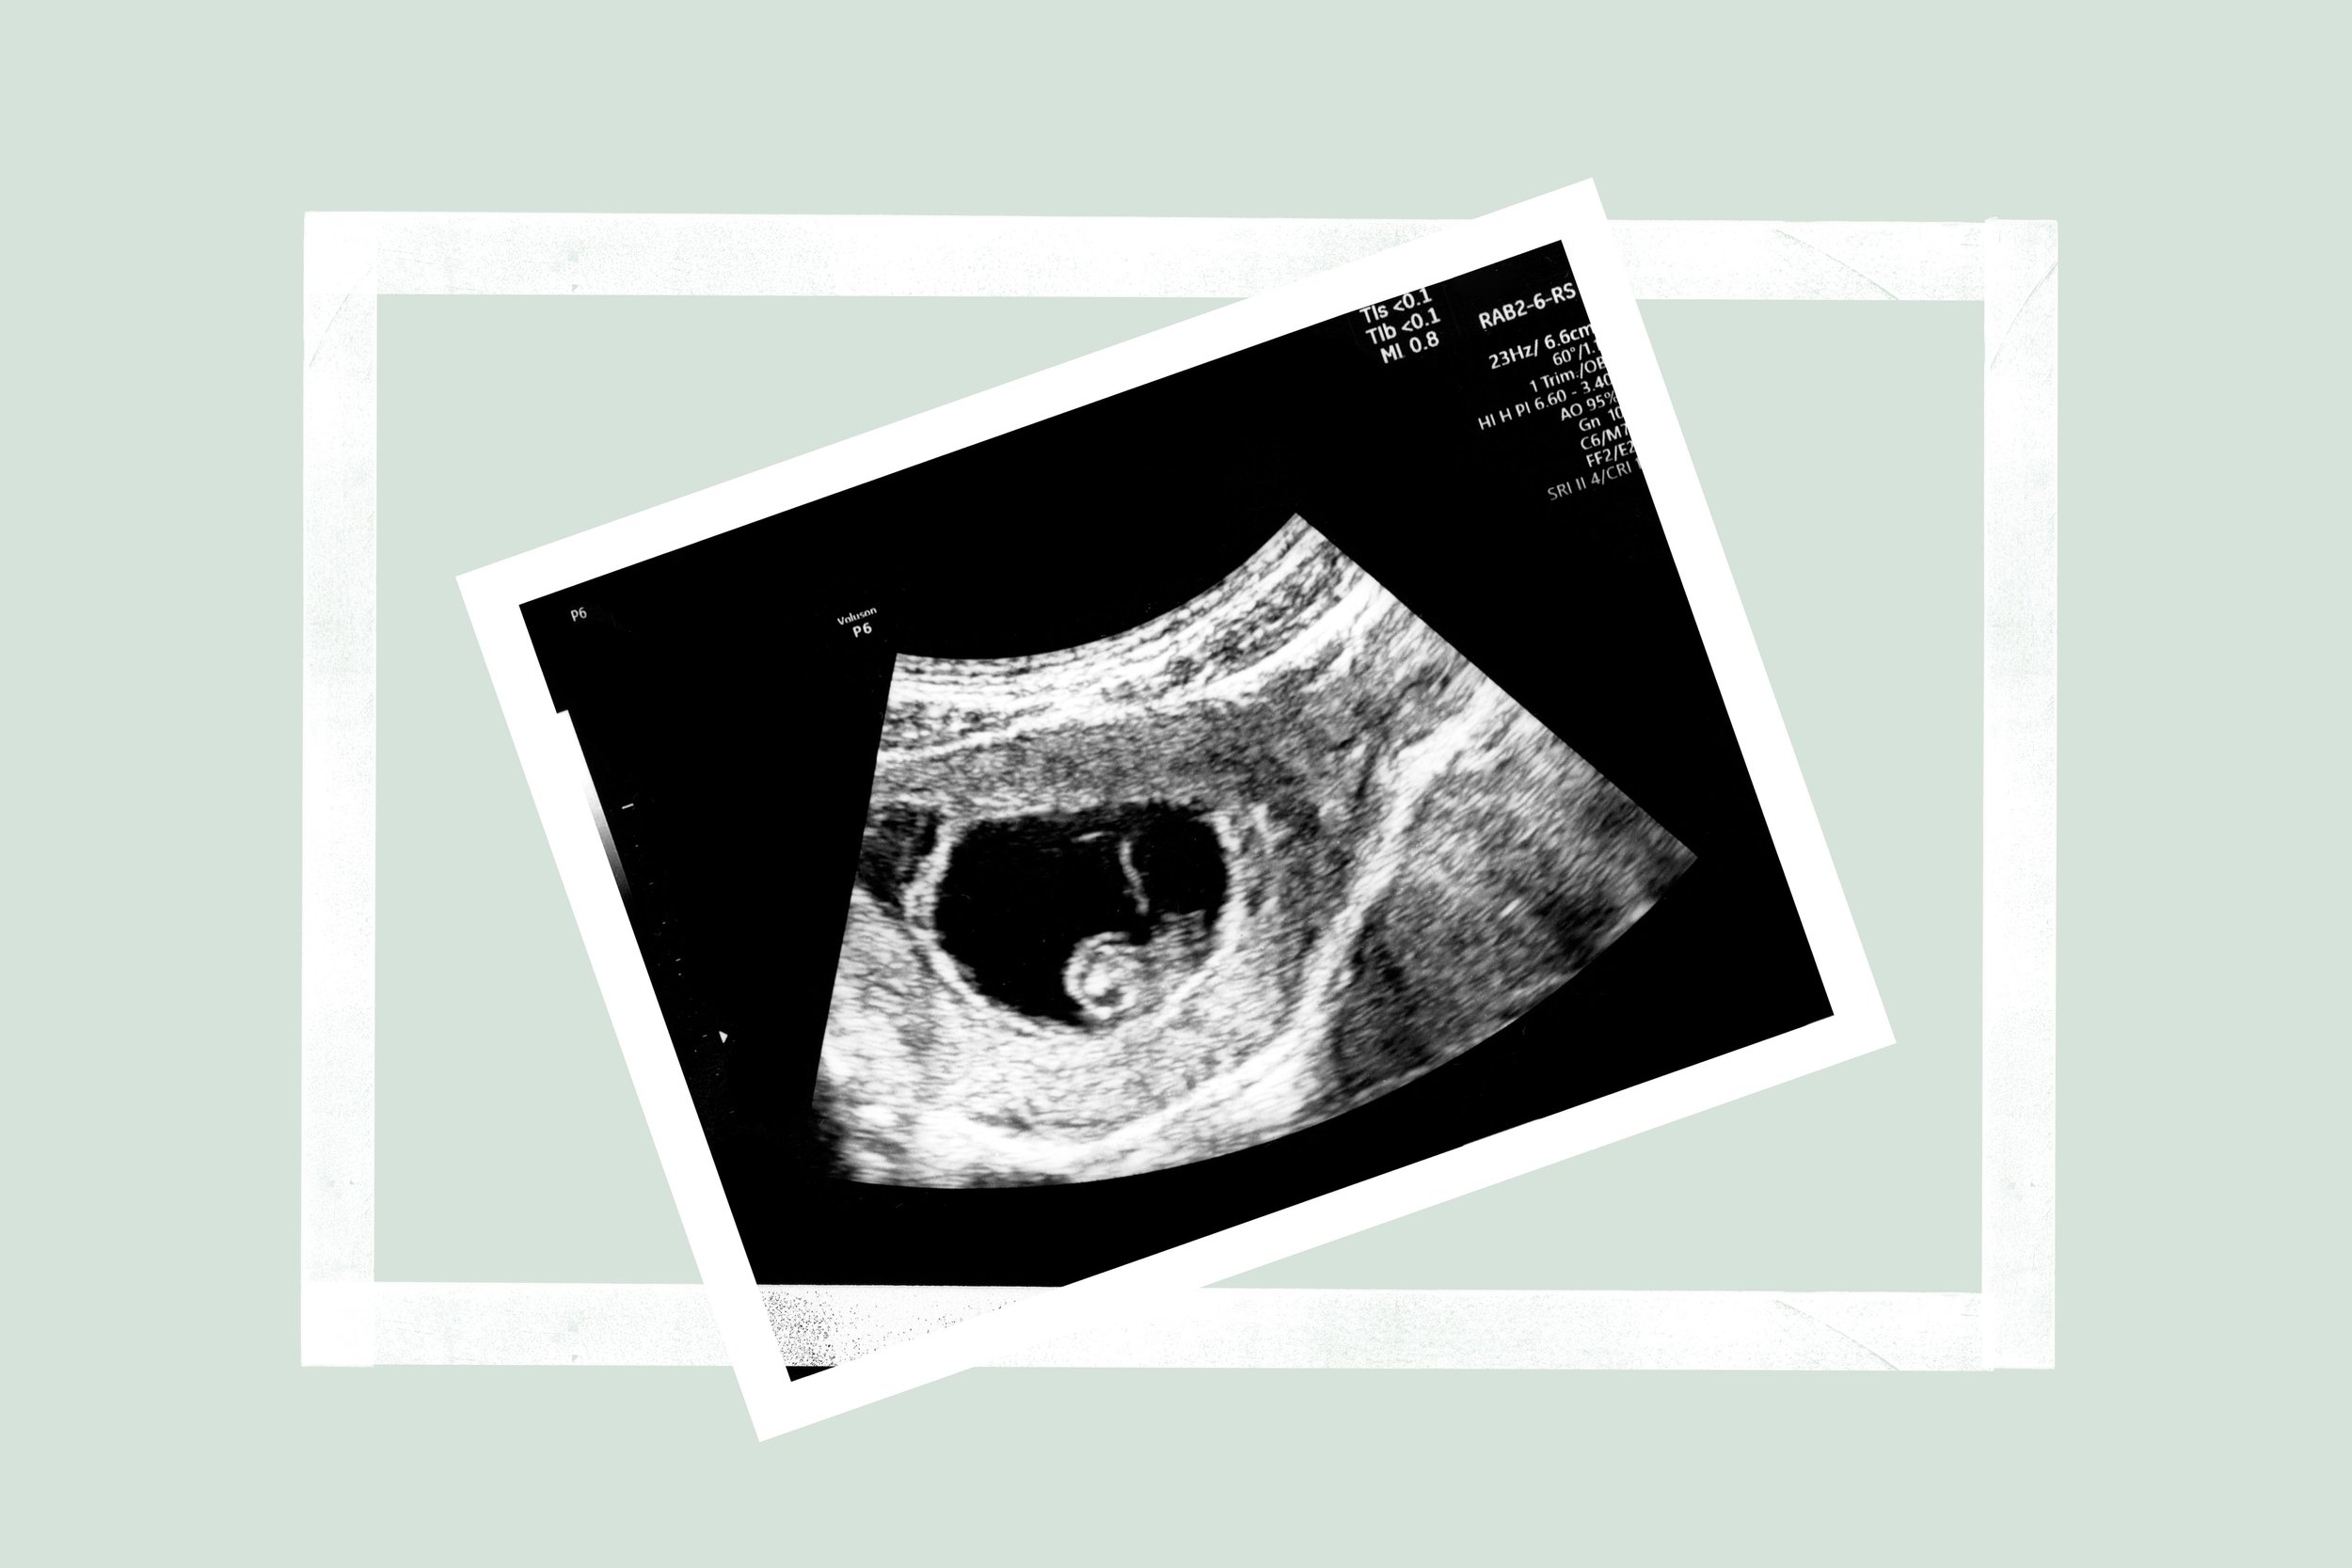

The dating scan is the first routine scan of pregnancy and will perhaps be the first time you have seen your baby, unless you’ve had an earlier scan for any reason.

It is normally offered between 10-14 weeks of pregnancy and is most commonly done during the 12th week. It’s referred to as the dating scan as this is when the sonographer will see how far along your pregnancy is and they will also do a detailed check of your baby’s development. It is often carried out alongside a blood test and together these tests form part of the screening programme for conditions such as Down’s syndrome.

A sonographer will put some gel on your tummy and use an ultrasound probe to get 2D images of your baby on their screen. You may see them taking lots of measurements and notes but please don’t worry, this is normal. They will explain their findings and also give you photos to take home with you.